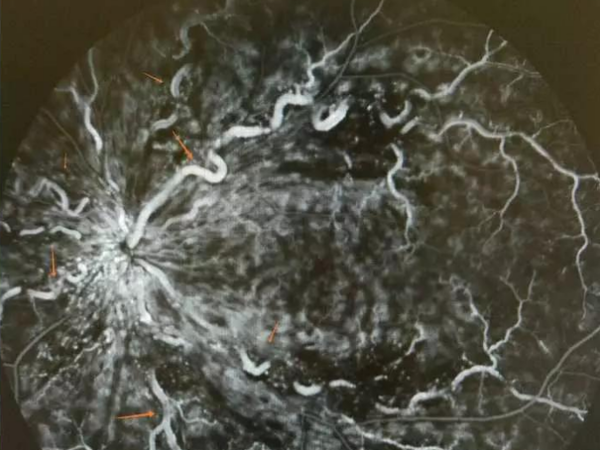

【震驚】23歲小伙眼睛里現"蚯蚓"爬行,病因讓他萬分后悔,80%的年輕人有可能換上這病!

一個月前,23歲的小王忽然看東西覺得都在云里霧中,變得模模糊糊,在浙江省醫院眼科檢查后,發現小王的眼晴“中風"了。 他的右眼患上了視網膜中央靜脈阻塞,眼底的血管因阻塞像蚯蚓般扭曲“爬行”,這個總是出現在老年人身上的“眼中風”,原來和小王經常熬夜疲勞有關系。